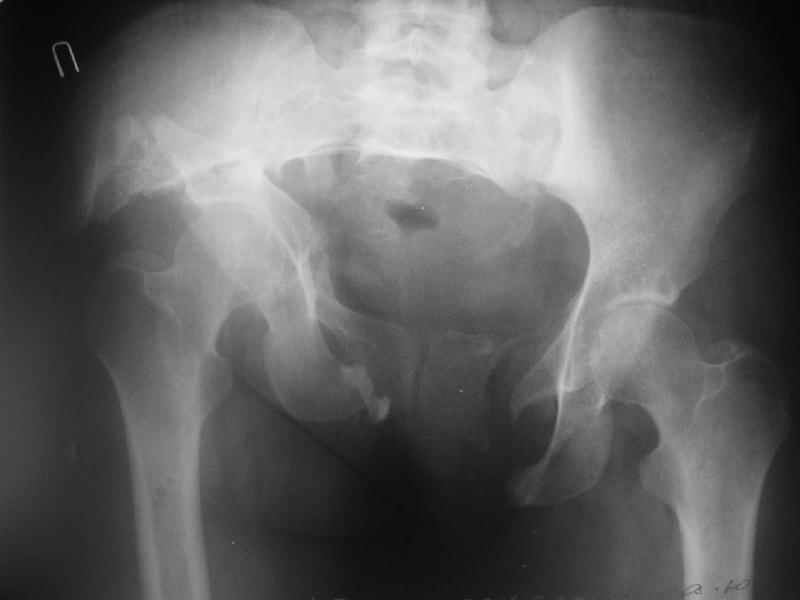

Госпитализирована больная 27 лет. Травма 1.5 года назад, сбита авто. При поступлении в местной больнице наложен фиксационный аппарат-«передняя рама». Через месяц аппарат снят из-за нагноения, разрешена ходьба с костылями. В послеоперационном периоде отмечалось нагноение забрюшинной гематомы. При обрашении к нам 3 мес назад в области промежности имелся свищ, по месту жительства выполнено иссечение свища, был гнойный затек на бедре, откуда получено до литра гноя, больная ходила с костылями.Свищ зажил 1,5 мес назад При поступлении сейчас укорочение до 5 см, ходит без дополнительной опоры, имеется выраженная хромота.Какой, по вашему, может быть оптимальная тактика оперативного лечения? Ограничиться низведением вертлужной впадины (каким доступом?), выполнить полную реконструкцию передних и задних отделов, одномоментно или поэтапно? Заранее благодарен.

In other hand, I would like to see the primary X rays, because with 3D-CT alone I cannot classify that fracture into Letournel's classification. Maybe it is a posterior hemitransverse with anterior column fracture.

По просьбам коллег отправляем снимки таза: прямая, inlet, outlet, 2 дополнительные компьютерные томограммы.